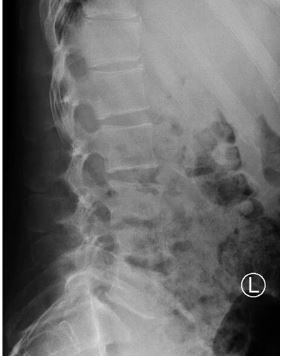

Relevant imaging results

Radiograph, lumbar spine